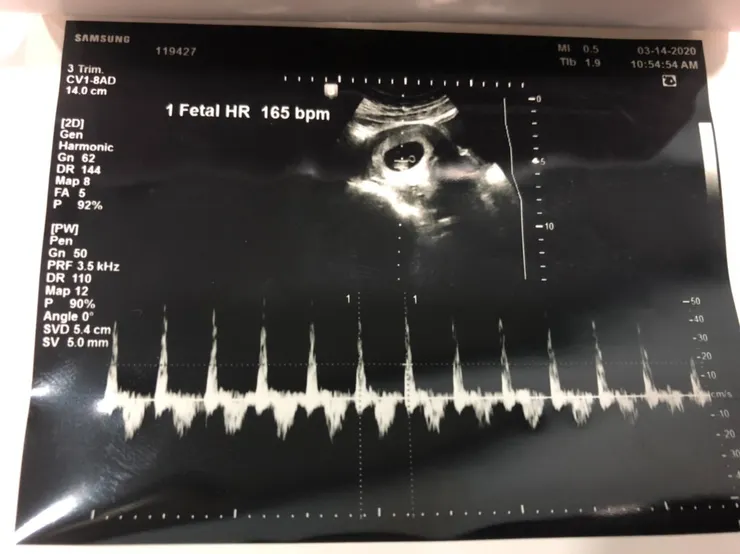

抱著期待興奮的心情去產檢,第一次聽到寶寶強而有力的心跳聲,感受到生命的奧妙,那是全世界最令人感動難忘的美妙聲音。